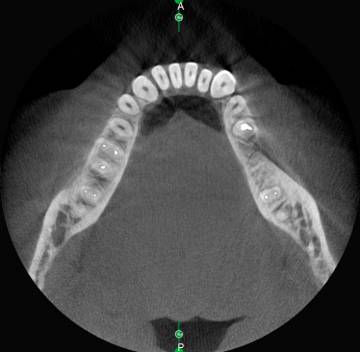

Позволяет быстро оценить плотность кости и измерить ее объем.

- Демонстрирует плотность кости пациента вокруг имплантата за один щелчок!

- Повышает частоту успеха имплантации благодаря надежной оценке качества кости

- Позволяет легко оценить плотность кости для более эффективной остеоинтеграции